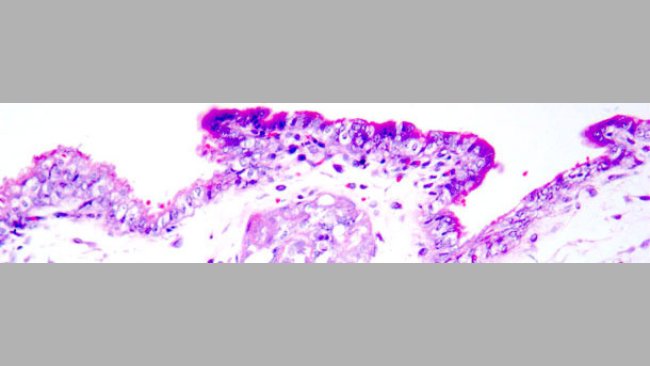

Lésions et signes des principales maladies du porc